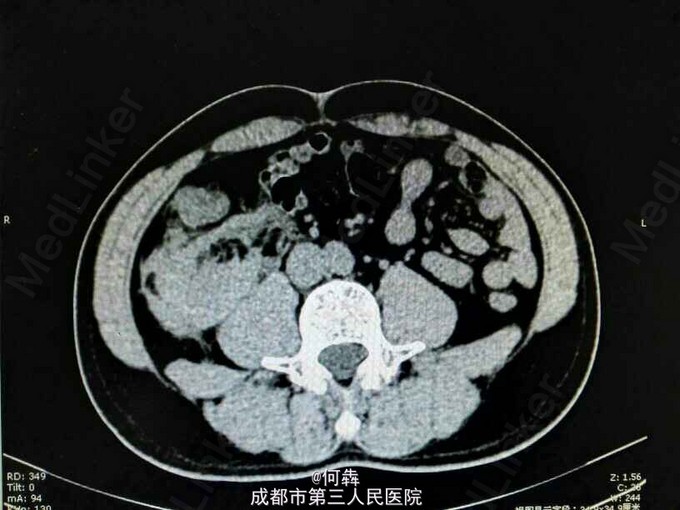

48岁男性,因“突发右腰痛1小时”入院,无血尿、外伤。既往无高血压、糖尿病。

右肾区扣痛阳性,余阴性。

右肾占位伴出血。入院后6天在全麻下行右肾部分切除术。术中冰冻及术后病检见图片

肾上皮样血管平滑肌脂肪瘤(EAML)是肾血管平滑肌脂肪瘤的一种少见亚型。2004版WTO肿瘤分类定义为一种具有恶性潜能的间叶性肿瘤。诊断时则往往与肾细胞癌相混淆。近年较多文献报道,部分EAML易局部复发、侵袭性生长、静脉侵犯、淋巴结或远处转移(以肝和肺转移为主),其预后不佳。